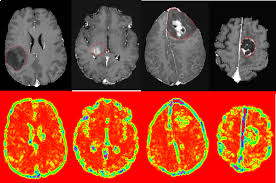

Are Brain Tumors Increasing : 10 Most Common Brain Tumor Symptoms Signs Of Brain Cancer : People who notice changes in the frequency or intensity.. Brain tumors can increase pressure, damage, and destruction on surrounding tissue and nerves, block pathways that transport cerebrospinal fluid, and alter brain functions. Gliomas begin from glial cells, which make up the supportive tissue of the brain. In children, most brain tumors are primary tumors. A brain tumor occurs when abnormal cells form within the brain. Brain tumors can be deadly, significantly impact quality of life, and change everything for a patient and their loved ones.

Some people with several risk factors never develop a brain tumor, while others with no known risk. Malignant primary brain tumors are cancers that start in your brain, typically grow faster than benign tumors, and quickly invade surrounding tissue. Cns tumor is a generic term encompassing over 120 distinct tumor types. Brain tumors may originate from neural elements within the brain, or they may represent spread of distant cancers. Malignant brain tumors are generally more serious and often are life threatening.

Illustration Of Different Of Brain Tumor Types And The Corresponding Download Scientific Diagram from www.researchgate.net Primary brain tumors include any tumor that starts in the brain. A brain tumor is a tumor that begins in the brain is called a primary brain tumor. Brain tumors refer to mass of abnormally growing cells in the brain. Rather more than 50 per cent are malignant with however, benign brain tumours can in general be cured. Malignant brain tumors are sometimes called brain cancer. As the tumor grows, it creates pressure on and changes the function of surrounding brain tissue, which causes signs and symptoms such as headaches, nausea and balance problems. Brain tumors are found in about 2% of routine autopsies. Sometimes some brain tumors begin in the brain, while others emerge in the brain due to another type of cancer that is in the body.

Tumors in the pons are called pontine gliomas (or diffuse intrinsic pontine midbrain tumors may cause eye symptoms similar to pontine gliomas, along with headaches and vomiting. Primary brain tumors originate from brain cells, whereas secondary tumors metastasize into the brain from other organs. Malignant brain tumors are generally more serious and often are life threatening. Depending on the size of the tumor and the regions of the brain affected symptoms may be expressed by motor, cognitive, or. Know the types, grades, causes, signs, symptoms, treatment of brain tumor. In children, most brain tumors are primary tumors. Cell phones aren't proven to cause brain cancer. A central nervous system tumor (cns tumor) is an abnormal growth of cells from the tissues of the brain or spinal cord. Brain tumors may originate from neural elements within the brain, or they may represent spread of distant cancers. A tumor that develops in any area of the brain stem is called a brain stem glioma. The increase appears to have accelerated in the last ten years according to the data from the danish cancer registry, analyzed by the swedish radiation protection foundation. Brain tumors refer to mass of abnormally growing cells in the brain. A brain tumor increases the pressure inside the skull, which can lead to inflammation and tissue damage.